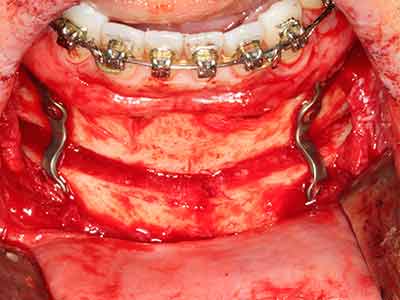

El tejido óseo no solo tiene un contenido puramente mineral, sino que también presenta una importante proporción de fibras de colágeno. Esto no solo garantiza una buena resistencia a la presión, sino también una cierta flexibilidad, que puede aprovecharse para la realización de aumentos. En la plastia de expansión clásica a efectos de una partición ósea, la cresta maxilar atrofiada se divide en su eje longitudinal y, tras alcanzar una profundidad de osteotomía suficiente, se extiende con cuidado (fig. 13-16), en un caso ideal sin desperiostizar de forma visible el maxilar (Brugnami, Caiazzo et al. 2014, Stricker, Fleiner et al. 2014). Los sistemas de tornillos y placas con distancia de expansión creciente han demostrado su eficacia para distanciar entre sí las dos tablas óseas por debajo del umbral de rotura. Por regla general, se requieren anchuras de hueso residual de al menos 3 a 4 mm (Chiapasco, Zaniboni et al. 2006) para garantizar una flexibilidad y una cobertura ósea suficientes de los implantes que van a incorporarse. En caso necesario, una osteotomía de descarga vertical unilateral o bilateral puede mejorar la flexibilidad. Como alternativa a la técnica clásica se ha descrito una combinación con otras técnicas de aumento, sobre todo en la parte bucal.

Con el uso de sierras piezoeléctricas la división se efectúa de forma especialmente cuidadosa y sin pérdidas importantes de las dimensiones, por lo que no se han encontrado diferencias significativas entre los implantes realizados en el maxilar dividido y en la cresta alveolar no deficitaria (Chiapasco, Zaniboni et al. 2006, Danza, Guidi et al. 2009). No obstante, precisamente en la partición profunda y limitada de forma local, es preciso asegurarse de que exista una adecuada irrigación por agua para evitar que se produzcan sobrecargas térmicas en las áreas de osteotomía apical.